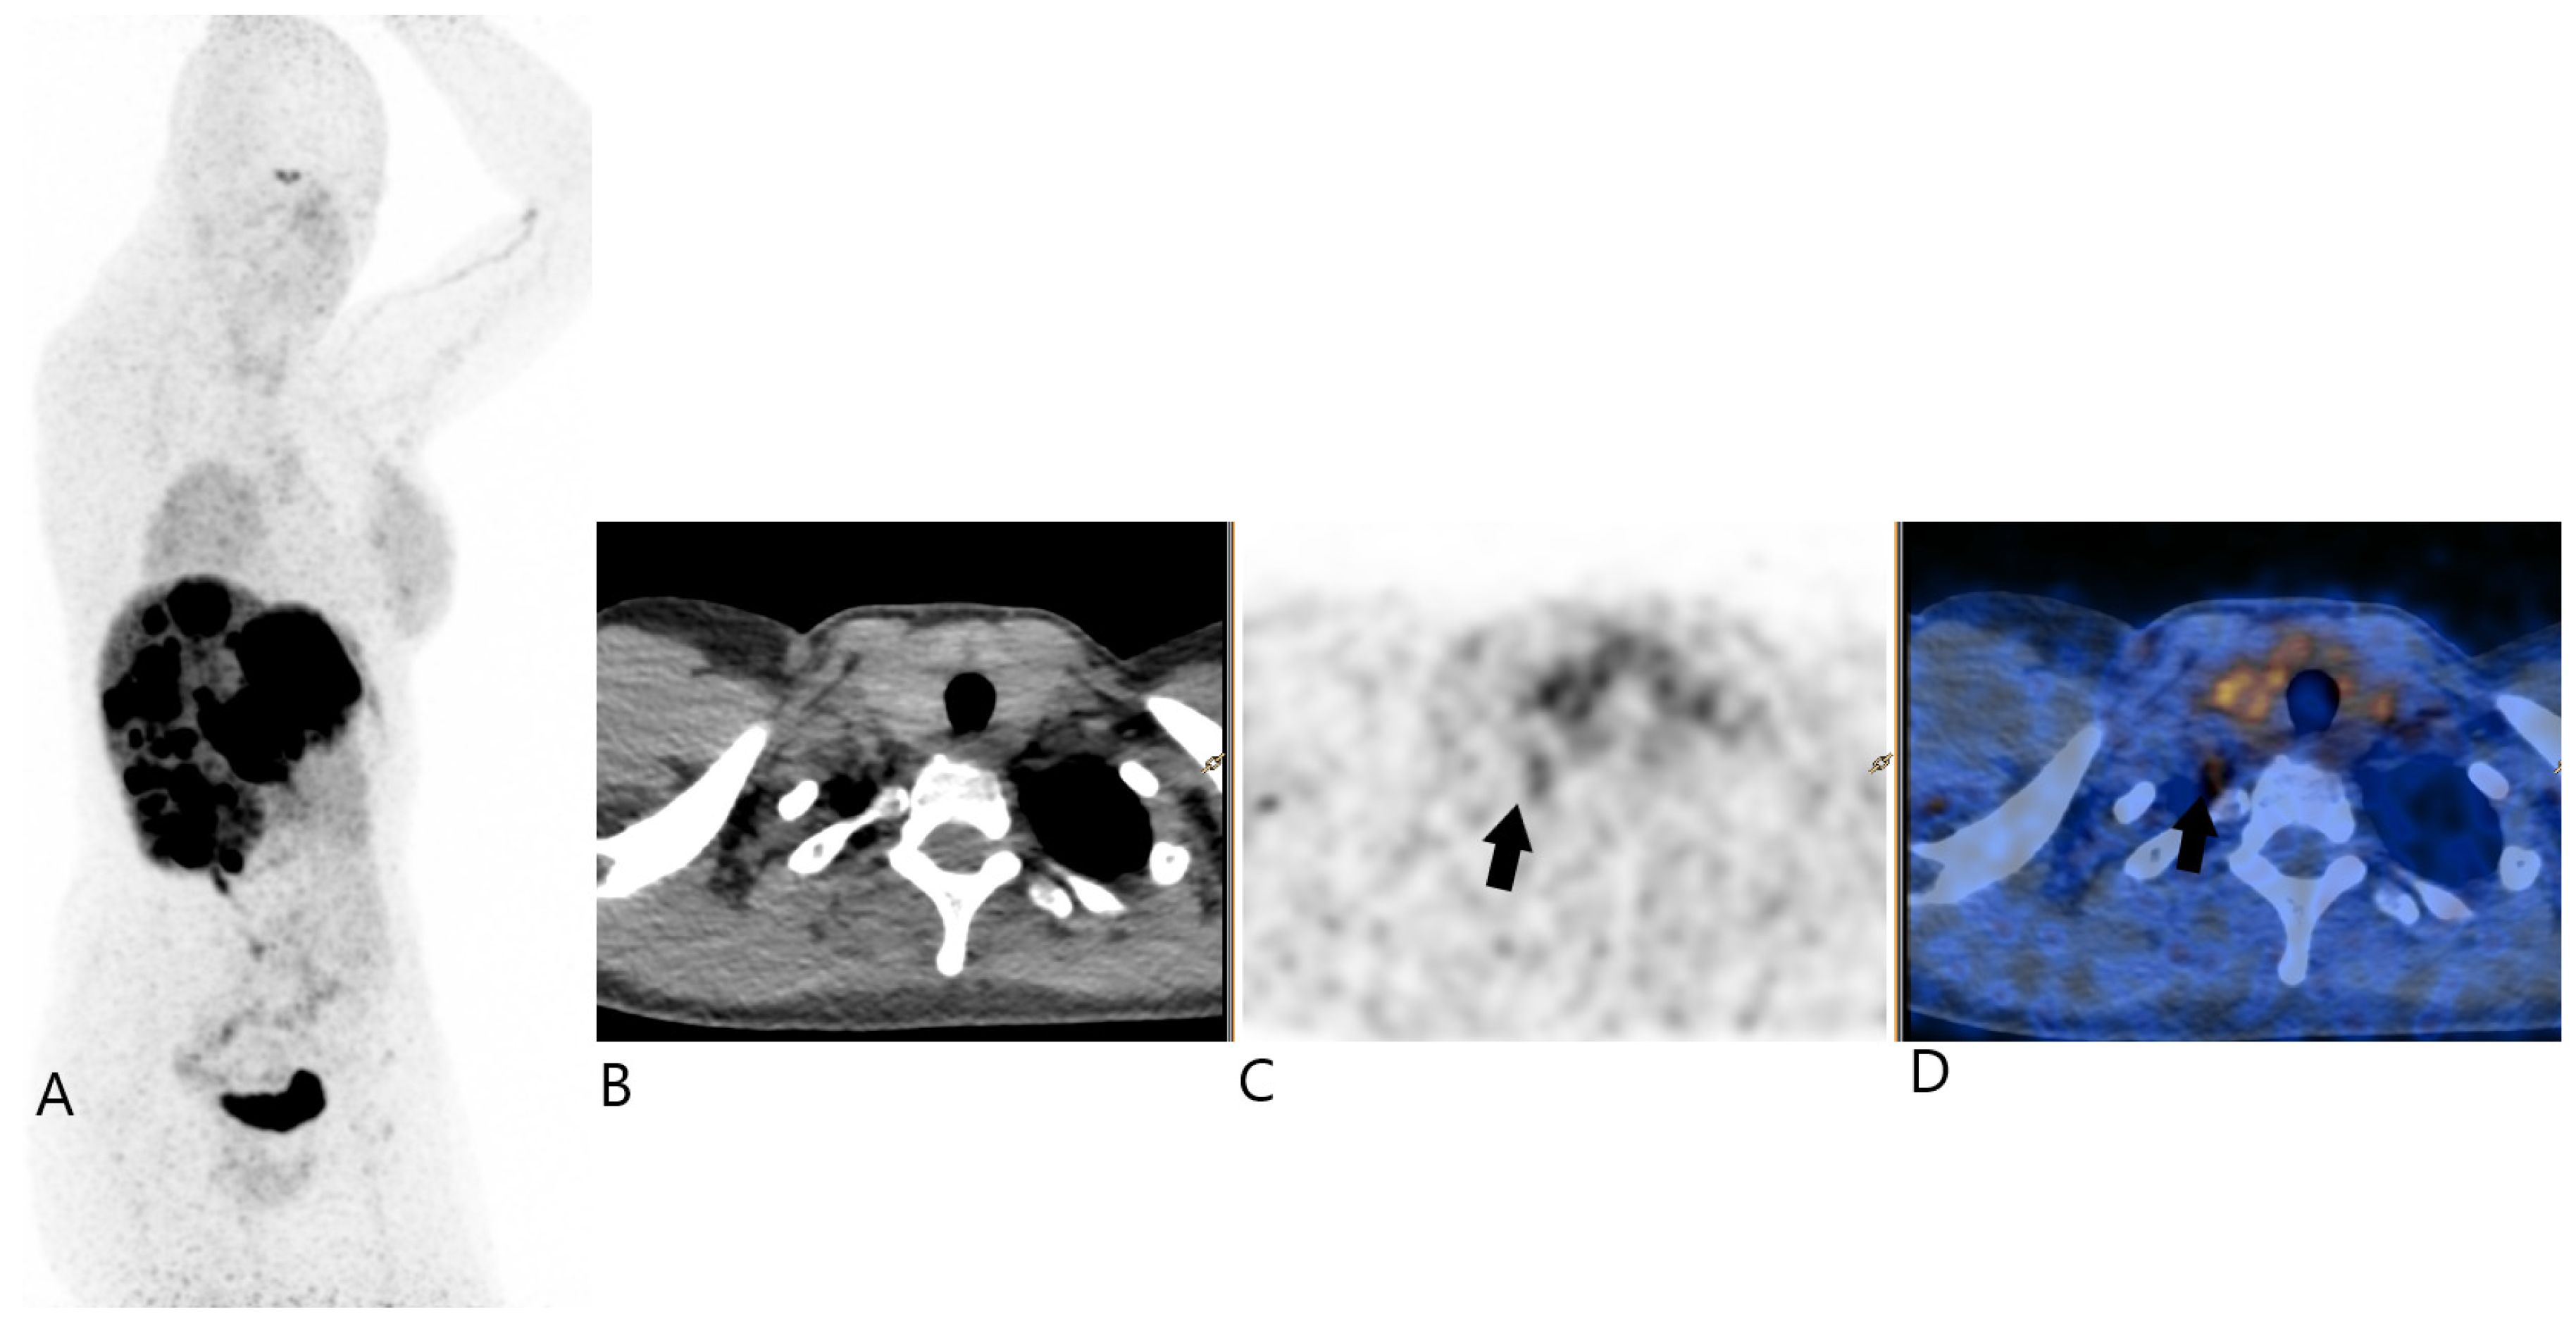

2. Case Report